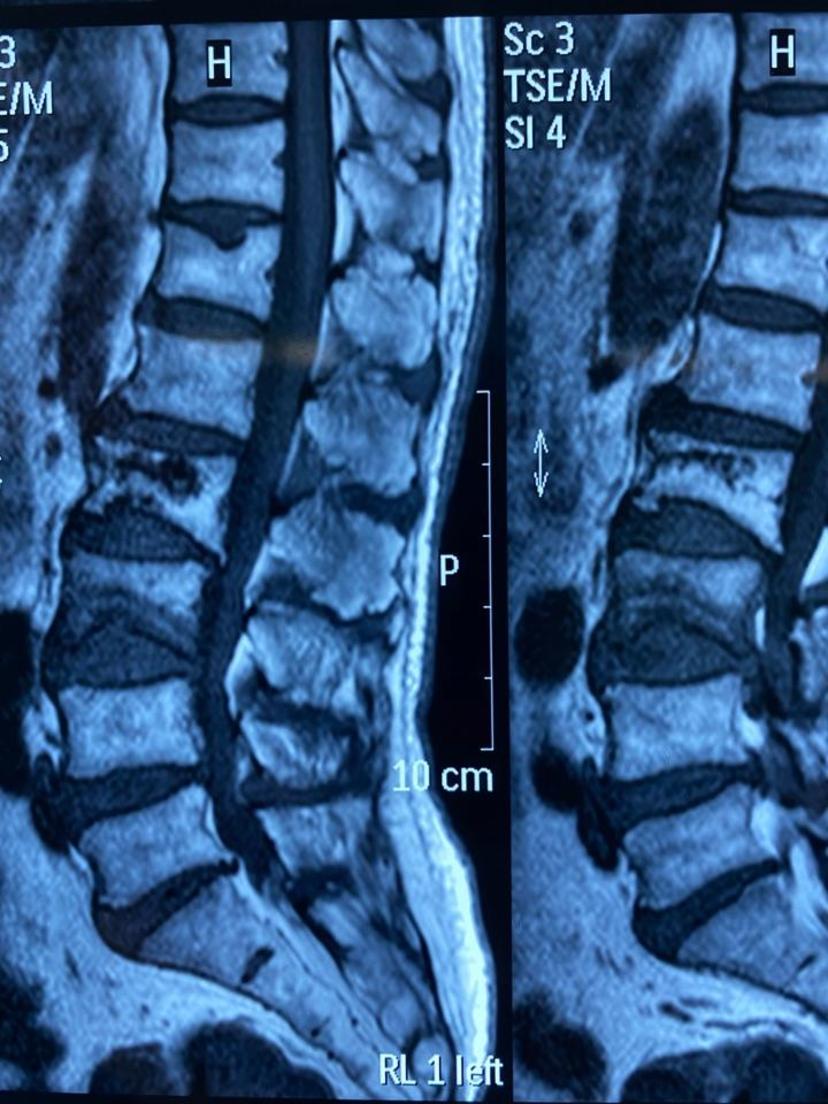

80岁老爷子因骨质疏松几年前腰椎发生过一次骨折,这次无明显外伤史再次感腰背部疼痛难忍、不能站立行走、卧床翻身困难,经腰椎磁共振及骨密度检查(诊断腰3椎体压缩性骨折、骨质疏松症),在局部麻醉、G臂机定位下行骨水泥灌注微创手术治疗,回病房后腰痛症状完全消失、床上翻身自如,术后次日早上康复出院!在此提醒患有骨质疏松的高龄患者,建议正规抗骨质疏松治疗、适当补钙、多晒太阳、适当户外运动,避免弯腰搬重物、谨防摔跤,一旦出现严重腰背痛、影响生活,建议到正规医院就诊。腰椎磁共振显示腰3椎体压缩骨折

磁共振示:腰3骨折、椎体下缘部分缺如